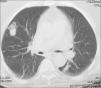

Mujer de 64 años con nódulo pulmonar e hipertensión arterial